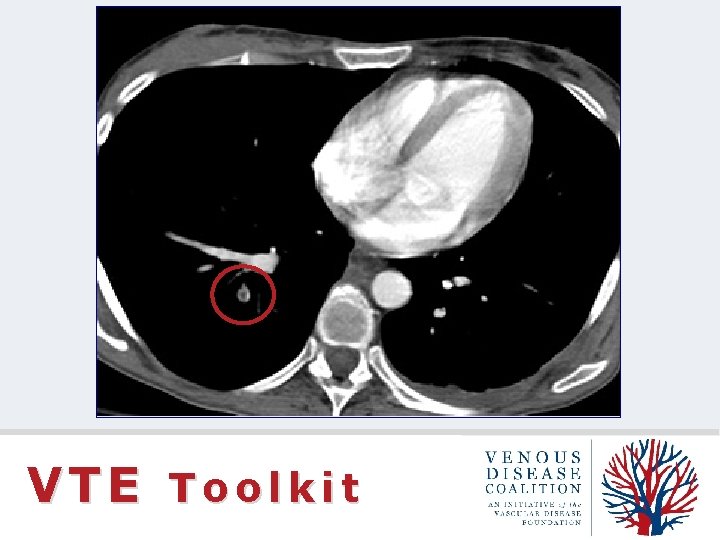

CT Pulmonary Angiogram VTE Toolkit

VTE Toolkit